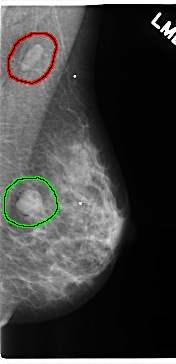

C_0212_1.LEFT_MLO

FILE: C_0212_1.LEFT_MLO.OVERLAY

TOTAL_ABNORMALITIES 2

ABNORMALITY 1

LESION_TYPE MASS SHAPE OVAL MARGINS CIRCUMSCRIBED

ASSESSMENT 5

SUBTLETY 5

PATHOLOGY MALIGNANT

TOTAL_OUTLINES 1

BOUNDARY

ABNORMALITY 2

LESION_TYPE MASS SHAPE ROUND MARGINS CIRCUMSCRIBED

ASSESSMENT 4